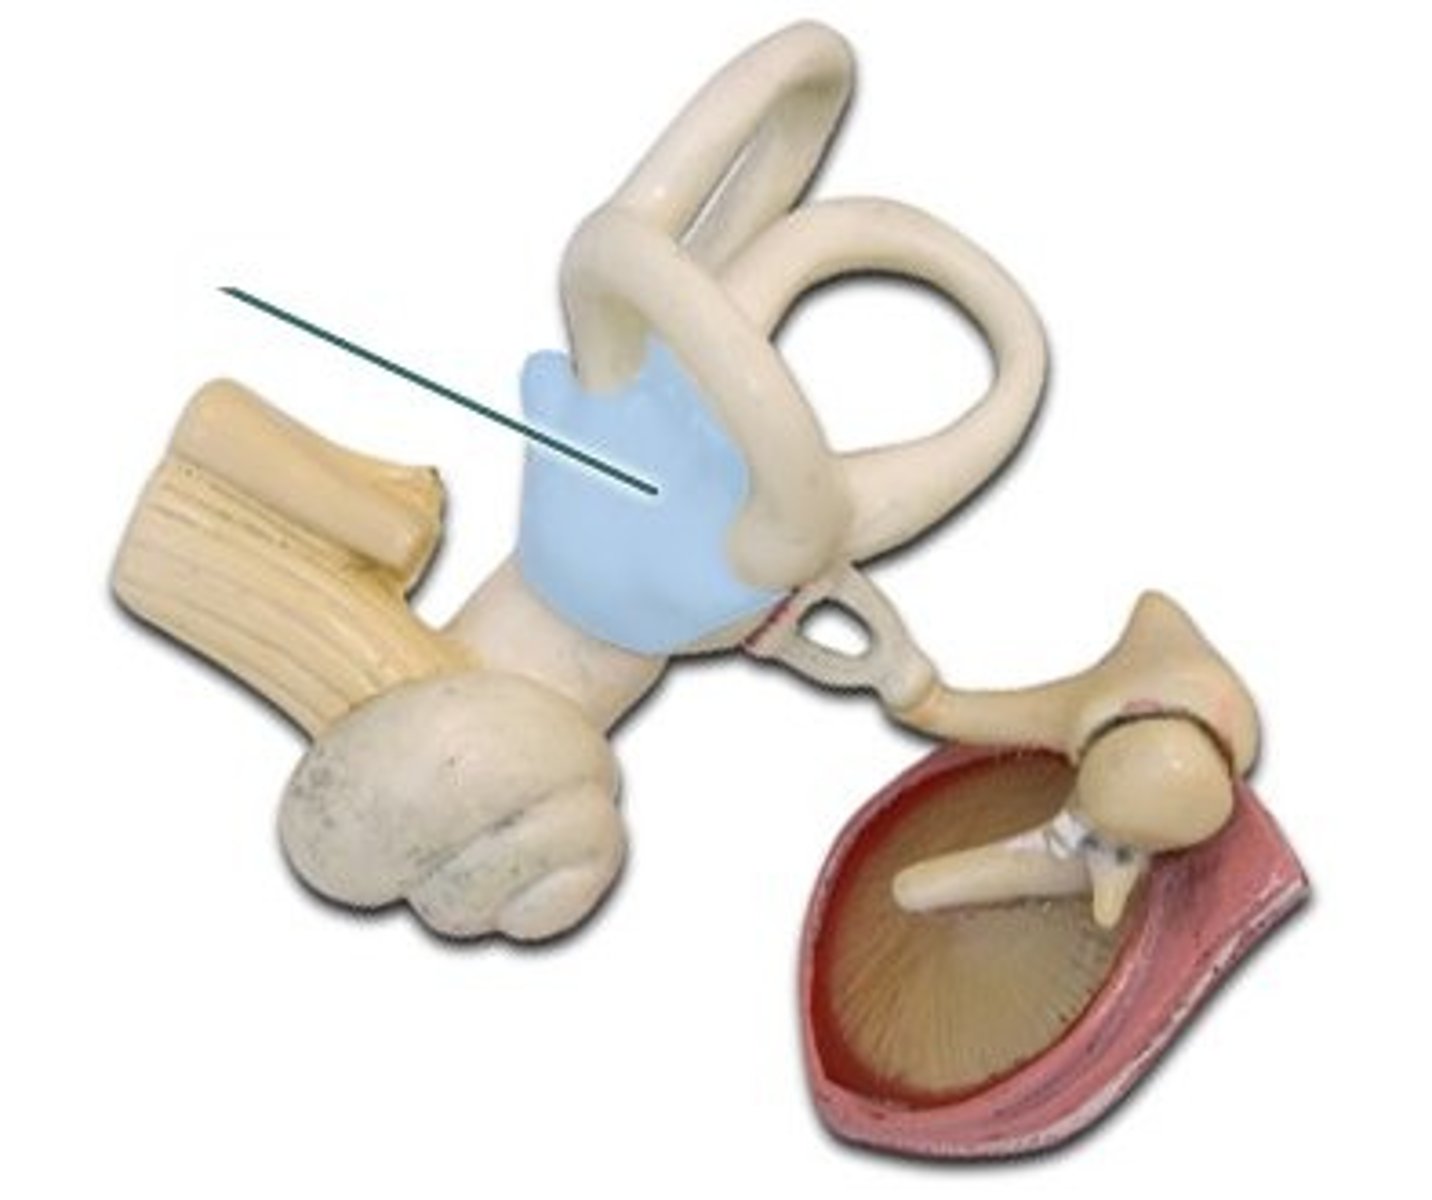

auditory tube

cochlea

incus

labyrinth (osseous + membranous)

malleus

oval window

round window

semicircular canals

stapes

temporal bone

tympanic membrane

vestibular nerve

vestibule

vestibulocochlear nerve